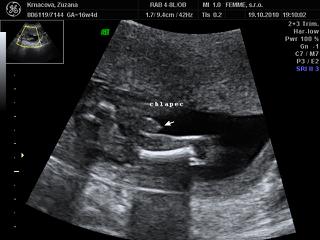

@petasllov no nas doktor nam vypocil termin na 2. april, ale po 3D a morfologii stale ultrazvuk vyhodil 1.4, ale nevadi ak to bude aj na den blaznov, hlavne nech je zdravi ved vynimka potvrdzuje pravidlo 😀 , aspon nikto nezabudne na jeho narodeniny 😵 a rodinu sme dopredu varovali, ze ak si malinky vyberie 1.4 termin a budeme im volat nech to neberu ako 1. aprilovy zart 😝